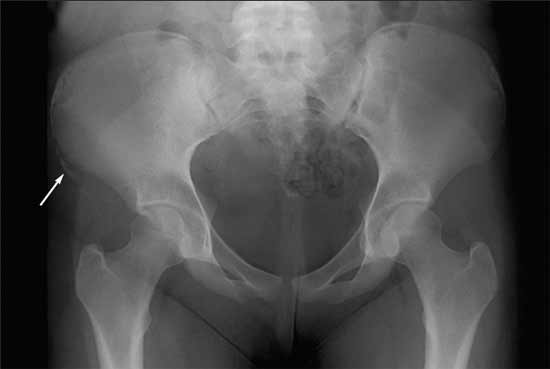

A 14-year-old girl came to the office with severe hip pain after she attempted a cheerleading maneuver on a trampoline. She was bouncing as high as she could and landed with her left knee flexed and her right hip extended. On impact, she felt a “pop” followed by right hip pain. After viewing her x-ray films, a radiologist diagnosed an avulsion fracture. The lower extremity is the most common body region injured on any type of trampoline. Fractures of the extremities occur frequently, but involvement of the trunk and pelvis is uncommon.

Image courtesy of Jean Someshwar, MD, J. Stephen Kroll, MD, and Linda S. Nield, MD.